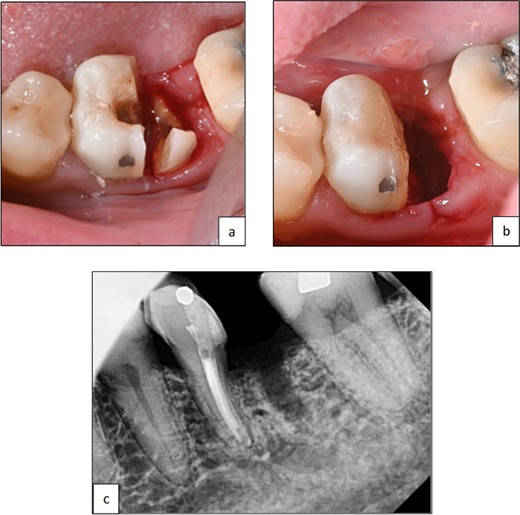

A 59-year-old male patient presented with a complaint of pain while biting on his lower left posterior teeth. Clinical examination revealed an extensive amalgam restoration on the lower left first molar (tooth 36) with a fractured restoration and secondary caries on the lingual aspect. The tooth was non-responsive to thermal testing and electrical pulp sensibility testing (EPT) and was tender to percussion. Radiographic examination showed radiolucency beneath the restoration on the mesial root surface, indicative of caries, along with furcation involvement and peri-radicular radiolucency. The tooth was diagnosed with pulpal necrosis and symptomatic apical periodontitis associated with extensive root caries (Fig. 6 and 7).

Clinical photograph of tooth 36 showing extensive amalgam restoration on mesio-occlusal-disto-bucco-lingual (MODBL).

Periapical radiograph of tooth 36 shows large radiopacity, indicating a restoration on the crown extending to the mesial root surface. Radiolucency was detected beneath restoration on the mesial root surface, indicating caries. Peri-radicular radiolucency was observed in the furcation region.